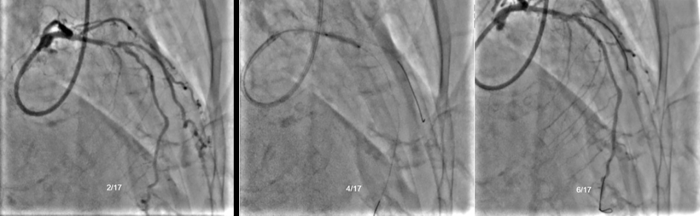

患者张先生(化名),73岁,因右侧股骨骨折收入创伤骨科,由于患者年龄较大且合并高血压、高脂血症等多种心血管危险因素,遂转入心内科评估冠脉血管,为骨科手术风险评估提供参考。冠脉造影提示前降支中远段全程弥漫病变,最重99%狭窄,回旋支中段完全闭塞,后降支有75%狭窄,术中仅对前降支血管进行了球囊扩张,术后给予双联抗血小板治疗。

(左)造影显示前降支中远段全程弥漫病变,最重99%狭窄,回旋支中段完全闭塞;(右)后降支和左室后支均有较重狭窄。

虽然患者身体各项机能均已衰退,手术风险较高,但通过手术固定骨折部位,能够减轻疼痛,便于日常护理照顾,减少卧床并发症。在患者家属强烈的治疗意愿下,李庭团队决定进行局麻下右侧股骨头置换手术,心内科指导术前控制血压稳定,维持扩冠、稳定斑块。在权衡缺血-出血风险后,心内科制定了围术期停用双抗,术后尽早恢复双抗治疗的方案。经过多个科室的通力配合,手术成功,术中出血约60ml。术后,患者在ICU停留1.5天后,回到CCU病房继续康复观察,围术期内无缺血-出血事件以及其他不良事件发生。术后恢复良好,于近日出院。